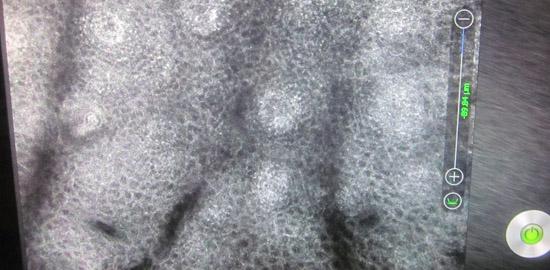

皮肤CT检查为发展期白癜风

根据对王老师问诊和借助于白斑诊断专业技术美国三维皮肤CT检查得知,王老师的白斑为发展期白癜风,黑色素为4级脱失,并存在潜在白斑。>>>我的白癜风又是哪一期呢?

高考后,学生们来看望王老师并汇报了各自的成绩,大都考得不错,王老师的心情变好了,加上医院的精心治疗,康复更快了。通过美国三维皮肤CT检测,黑色素细胞比初诊时明显增多,白斑肉眼观看几乎看不出来了。>>>我也想拥有这样的祛白效果?